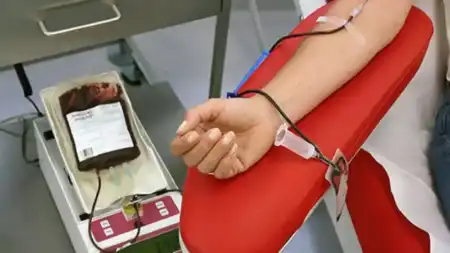

El Banco de Sangre recuerda a la comunidad las fechas previstas para las colectas voluntarias de donación de sangre que…